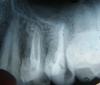

Limonzzza Опубликовано 3 декабря, 2010 Поделиться Опубликовано 3 декабря, 2010 (изменено) Уважаемые доктора - сегодня столкнулись лоб в лоб - стенка на стенку: распломбировывать или нет каналы, запломбированные гуттаперчей? Итак...Объективно мы имеем: Возраст 23 года, КПУ - 7, ИГ - 1,5, объект - зуб 2,5. Слизистая в области 2,5, гиперемирована, субодесневые сосочки отечны, гиперемированы, кровоточат при зондировании, причем дистальный отек больше и кровоточит сильнее. Мезиальная до уровня десны и 1/2 жевательной поверхностей покрыты пломбой, на контактно-дистальной поверхности зондируется кариозная полость. Сделали рентген, так как зуб был ранее лечен по поводу пульпита, 5 лет назад, ни разу не беспокоил, перкуссия безболезненна. После снятия пломбы обнаружилась большая кариозная полость, заполненная пигментированным дентином и остатками пищи, дистальная стенка разрушена полностью, под десну. Сосочек гипертрофирован. Пломбу сняли, мезиальная стенка была восстановлена очень достойно - оставили. Штифт выпелили. И вот тут как раз конфликт: канал запломбирован гуттаперчей. После удаления штифта осталось больше 2/3 запломбированного канала. Запломбирован плотно - ручной инструмент не входит, на рентгене сами видите - никаких изменений. Дальнейший план - естественно ортопедическая конструкция, и если не распломбировывать канал, то все понятно, а если распломбировывать, то потом запломбируем "только "Эодент" (финансовые сложности у пациента). И тут началось: надо сильнее файлом работать, может войдет. Ковыряли 15 минут, с сильным нажимом, наконец начали появляться опилки гуттаперчи. Распломбировка напоминала вбивание гвоздя в деревяшку молотком. Гуттаперча все-таки не паста - в канале не закаменеет, если ковырять по-любому сдастся. Как думаете? Изменено 3 декабря, 2010 пользователем Limonzzza Ссылка на комментарий

zybnaya feya Опубликовано 3 декабря, 2010 Поделиться Опубликовано 3 декабря, 2010 (изменено) Да,на РВГ картинка красивая и обтурация неплохая. все бы ничего,если бы не " кариозная полость". Гутта и силлер уже давно инфицированны. Что и является первопричиной и показанием для ретрита. Если нет специальных растворителей для гутты,купите в аптеке эвкалиптовое или лимонное эфирное масло. На браше точечно наносите на поверхность гутты. на глазах будет плавиться. Только мыть потом очень долго надо хлоркой с УЗ. ПыСы: вы такой широкий канал одним Эодентом заполнить хотите???? Будет несомненно овер,куча пор и ничего хорошего в плане прогноза. Нужна гутта однозначно. Изменено 3 декабря, 2010 пользователем zybnaya feya Ссылка на комментарий

Инс Опубликовано 5 декабря, 2010 Поделиться Опубликовано 5 декабря, 2010 Да,на РВГ картинка красивая и обтурация неплохая. все бы ничего,если бы не " кариозная полость". Гутта и силлер уже давно инфицированны. Что и является первопричиной и показанием для ретрита. Если нет специальных растворителей для гутты,купите в аптеке эвкалиптовое или лимонное эфирное масло. На браше точечно наносите на поверхность гутты. на глазах будет плавиться. Только мыть потом очень долго надо хлоркой с УЗ. ПыСы: вы такой широкий канал одним Эодентом заполнить хотите???? Будет несомненно овер,куча пор и ничего хорошего в плане прогноза. Нужна гутта однозначно.Если гутта и силлер давно уже инфицированны, то почему в периодонте нет изменений? Периодонтальная щель даже не расширена. Ссылка на комментарий

д-р Вит Опубликовано 5 декабря, 2010 Поделиться Опубликовано 5 декабря, 2010 Если гутта и силлер давно уже инфицированны, то почему в периодонте нет изменений? Периодонтальная щель даже не расширена.есть в периодонте изменения или нет по одному снимку невозможно определить,нужно КТ-шка и еще уметь с ней работать,а это сочетание не так часто встречается. Ссылка на комментарий